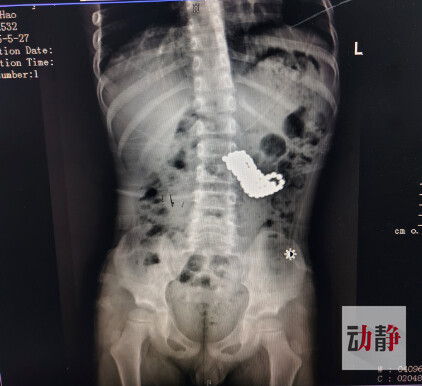

Ha tenido que ser intervenido quirúrgicamente para sacarle 123 cuentas que quedaron alojadas dentro de su estómago.

Radiografia

Según informa el hospital, tras más de cuatro horas de cirugía, en las que fue utilizado equipo especializado de gastroscopía, los médicos pudieron recuperar del estómago del menor las 123 cuentas de 0,5 centímetros cada una que había ingerido.

Pero la intervención por endoscopia fue complicada, ya que Xiao no solo tenía bolitas magnéticas formando un bloque en el estómago, sino también una gran cantidad de residuos de alimentos envolviéndolas. Afortunadamente todo salió bien y el pequeño no ha tenido secuelas.